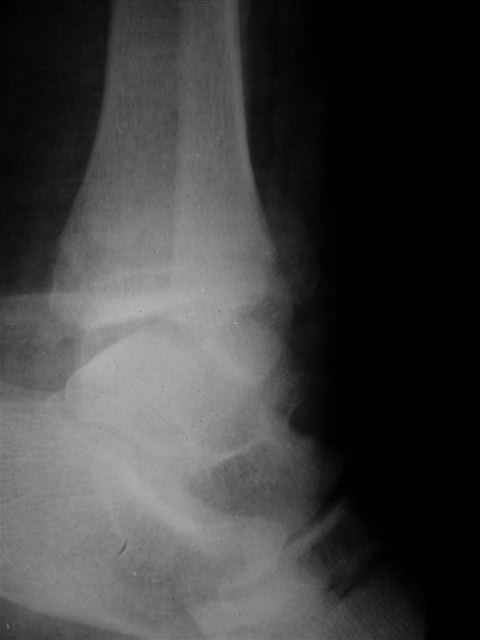

В первом письме я упомянул о закрытом повреждении правого голеностопного сустава, эверсионно-пронационный механизм травмы - перелом внутренней лодыжки( поперечный, на уровне суставной щели) и отрывной перелом бугорка Chaput. После обработки открытых переломов бедра и большеберцовой кости в эту же сессию перелом внутренней лодыжки фиксировал двумя расходящимися спицами, бугорок Chaput двумя тягловыми винтами 3,5 мм. Раны заживают благополучно. Учитывая повреждение наружной группы мышц, активное разгибание в голеностопном суставе ограничено. Пассивная + пассивно-активная мобилизация голеностопного сустава с физиотерапевтом.

Я предупреждал, что ничего сверхъестественного. Каюсь, что одна из спиц прошла несколько дальше, чем нужно было, но главное - перелом стабилизирован и больной работает суставом в полном объёме, несмотря на представленную раннее травму коленного сустава.